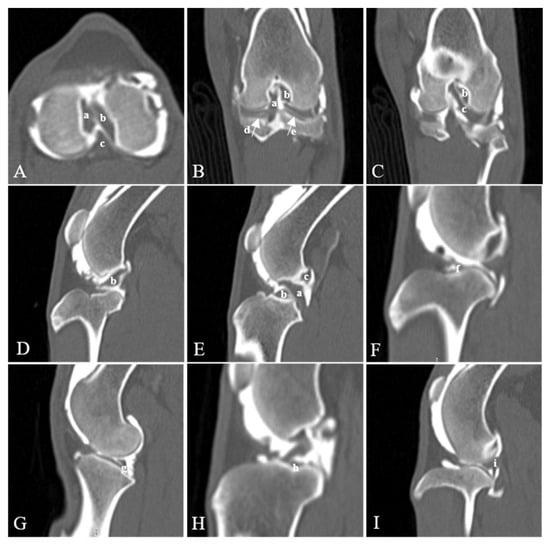

3.2. Qualitative Image Analysis of Visualization